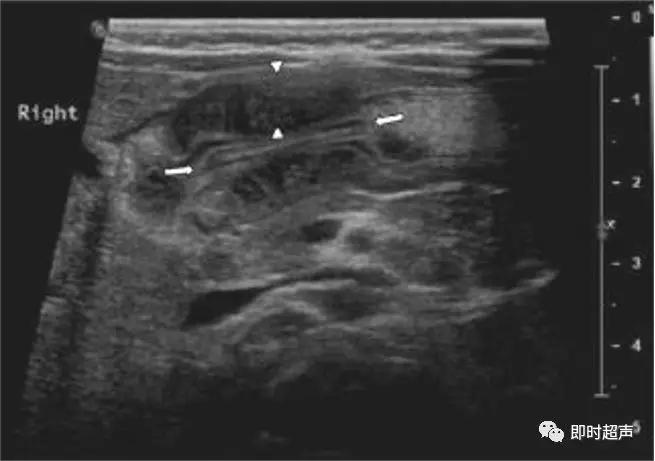

幽门肥厚狭窄声像图:

增厚的幽门肌层(三角箭头之间),增长的幽门管(长箭头之间)。

先天性肥厚性幽门狭窄

幽门纵切呈“宫颈征”。幽门横切面呈“靶环征”

均质低回声团:“宫颈征”

肌层厚 >4mm (正常<3mm)

幽门直径 >14mm

幽门管长 >16mm(正常<15mm )

管壁蠕动消失

胃腔扩张